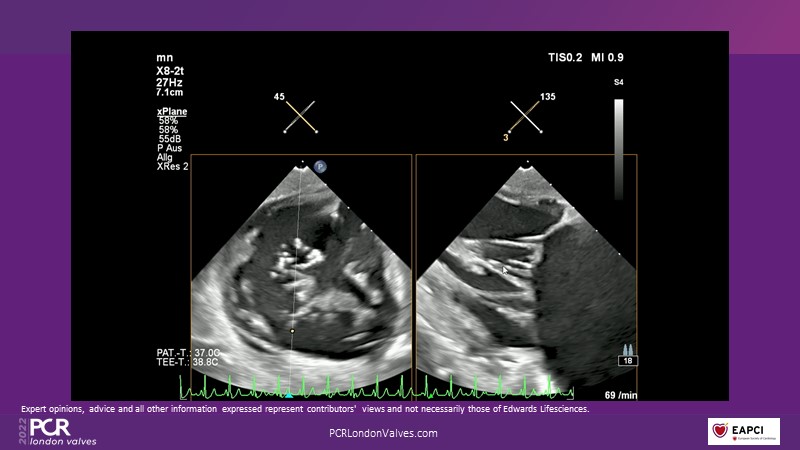

This innovative session takes you through the patient selection and anatomical characteristics when selecting amongst the different transcatheter options to treat tricuspid regurgitation, followed by a recorded demonstration using the PASCAL Precision repair system.